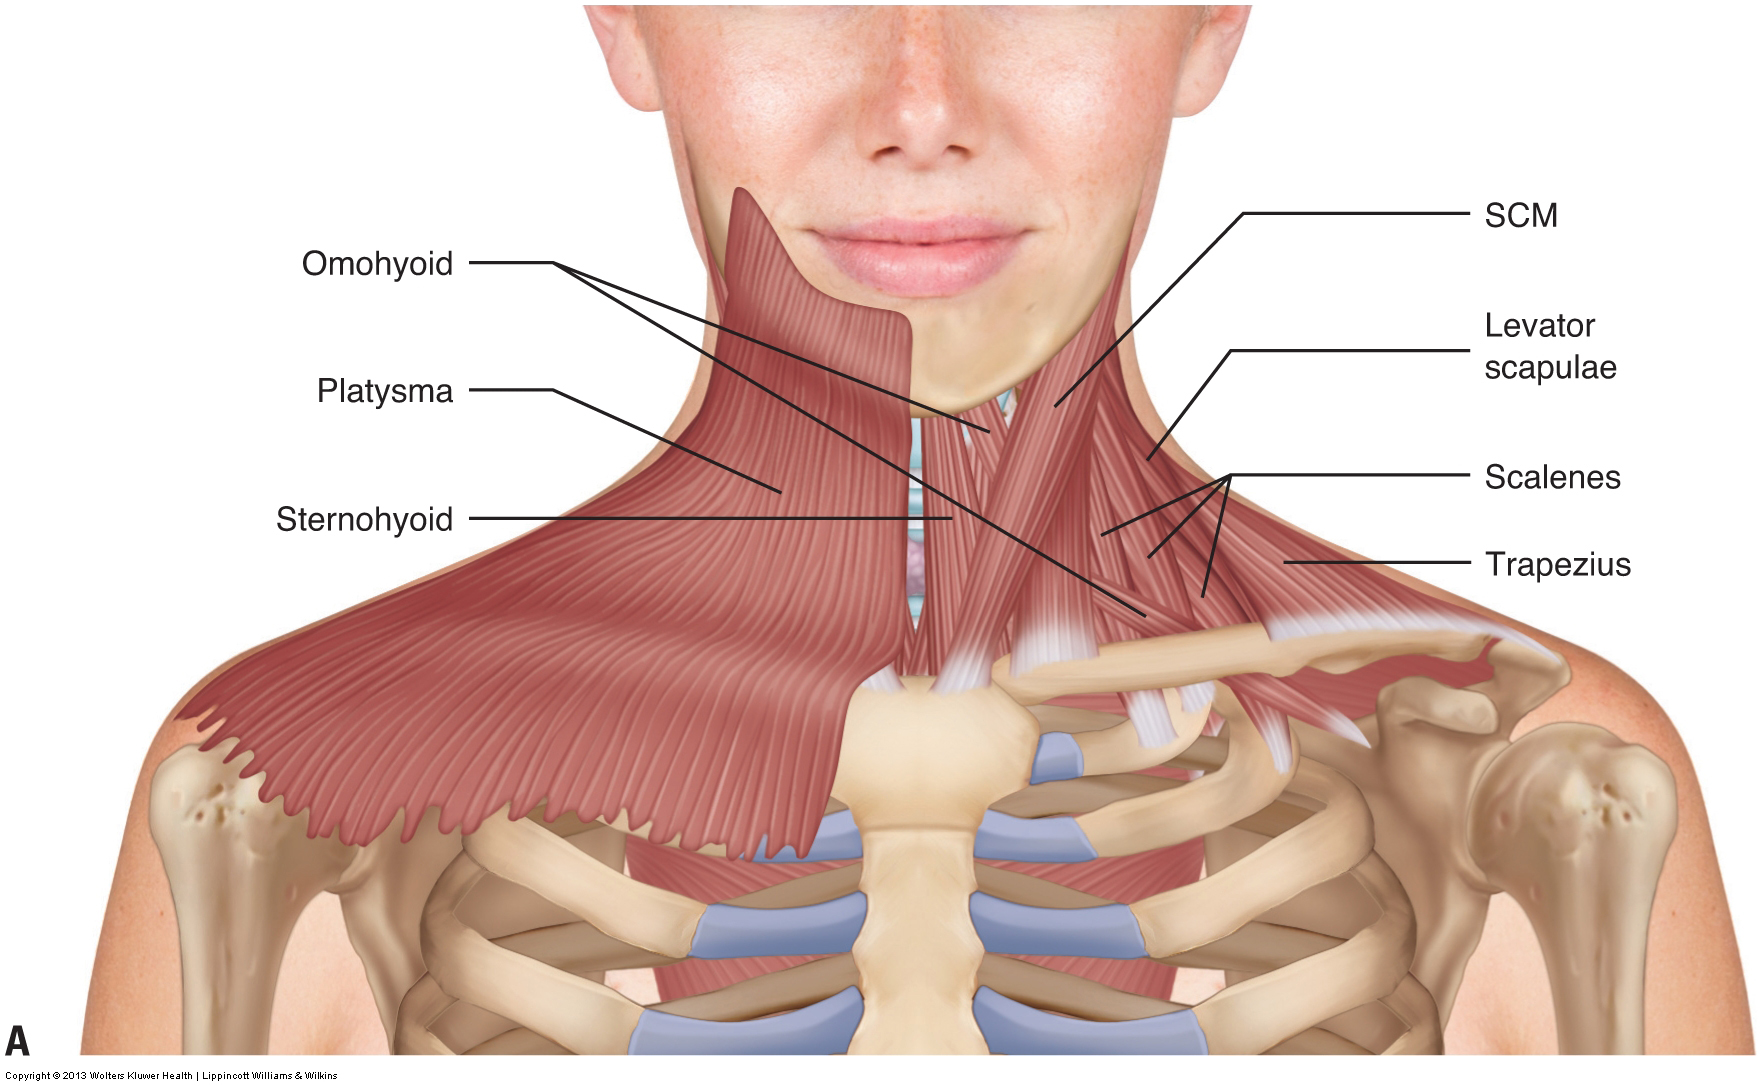

Neck Muscle Diagram Labeled Posted in diagrams scalenes muscles.

Muscles of the neck / musculature of the cervical spine